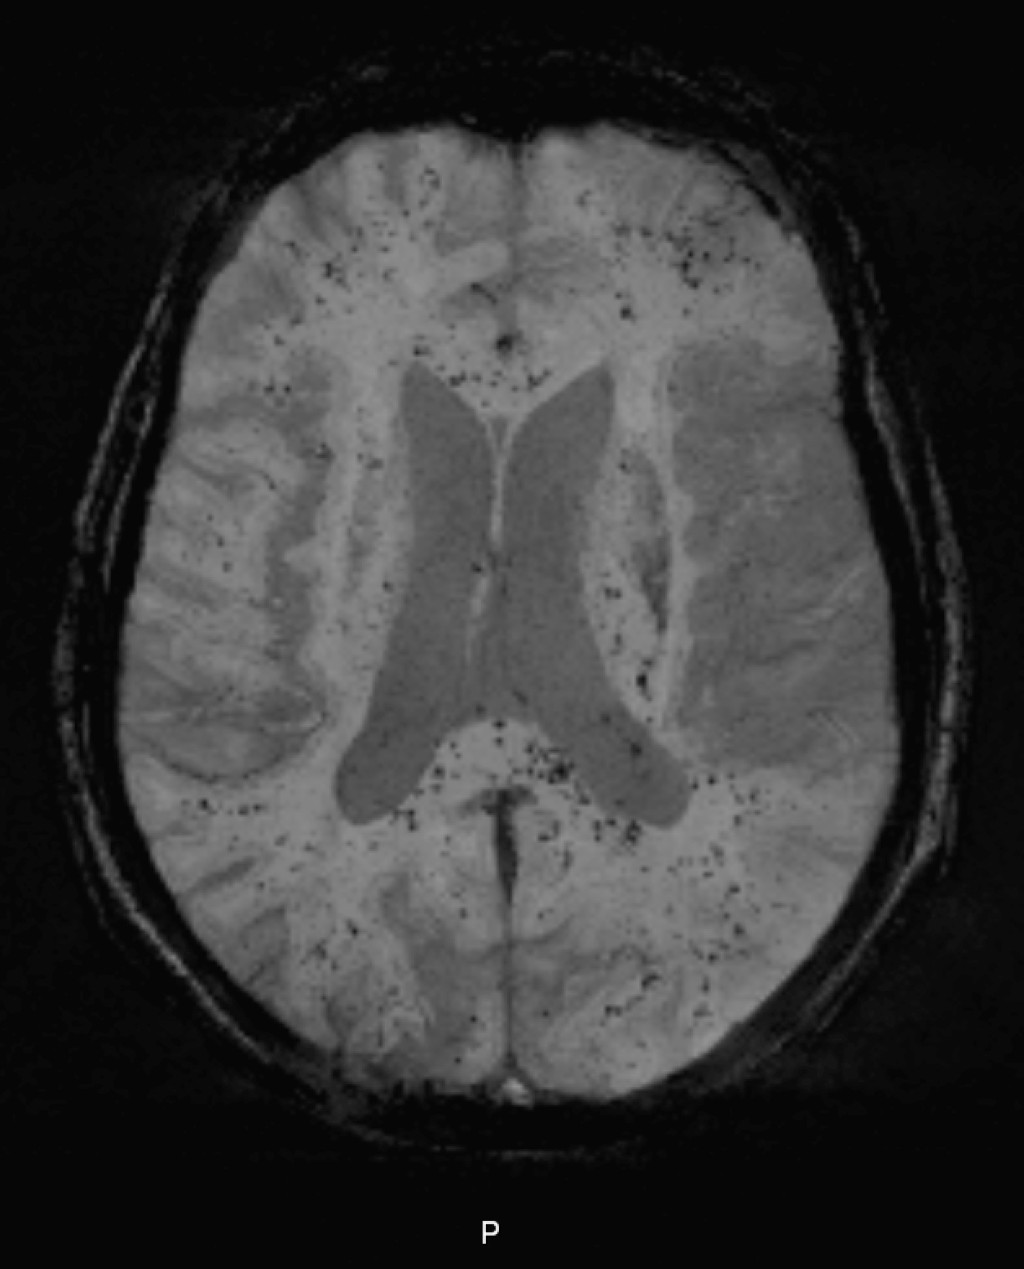

På dag 5 ble det gjort MR-undersøkelse av hjernen. Suseptibilitetsvektet sekvens (SWI) viste multiple, små mørke lesjoner som gjenspeilet nedbrytningsprodukter fra blod i hvit substans, corpus callosum og pons (gjengitt her). Diffusjonsvektet sekvens (DWI) viste noen små diffusjonsrestriksjoner hovedsakelig i cortex. Det førstnevnte bildet var uttrykk for små hemorrhagier/petekkier og det sistnevnte for små, ferske infarkter. Funnet stemte overens med cerebrale fettembolier (1).

Siden emboliske fettpartikler fører til okklusjon av kapillærer i hjerneparenkymet ville man forvente å se ferske, mikroemboliske infarkter med diffusjonsrestriksjon. De fleste av lesjonene var ikke ferske infarkter, men derimot primære petekkiale blødninger. Ellers hadde vi sett flere lesjoner med diffusjonsrestriksjon på samme lokalisasjon som hemorrhagier. En av teoriene for primære cerebrale petekkiale blødninger er at kapillarveggen ryker på grunn av økt trykk, forårsaket av emboli (1).

Blant de radiologiske differensialdiagnosene er diffus aksonal skade (diffuse axonal injury, DAI) og amyloid angiopati. Ved diffus aksonal skade ville man forvente mikrohemorrhagier hovedsakelig i grensesnitt mellom grå og hvit substans, men også i corpus callosum og pons. Pasienter med diffus aksonal skade har nevrologiske symptomer umiddelbart etter traume. Vår pasient hadde upåfallende MR-undersøkelse med SWI-sekvens fra 2010, noe som talte imot amyloid angiopati.

Verken små, ferske infarkter eller mikroblødninger kan oppdages ved CT-undersøkelse. Vår pasient hadde normal CT caput-undersøkelse. Det er kjent at SWI-sekvens har mye høyere sensitivitet for mikrohemorrhagier enn ”T2-stjerne”-sekvens eller såkalt hemosekvens. I motsetning til cerebral mikroemboli, på grunn av arteriosklerotiske plakk eller atrieflimmer, er cerebralt fettembolisyndrom et sjeldent MR-funn. Som hovedregel burde bildediagnostikken bare bestilles hvis det finnes terapeutisk eller prognostisk konsekvens.